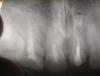

Gorod Опубликовано 16 января, 2007 Поделиться Опубликовано 16 января, 2007 Ситуация такова: зубы 21 и 11. Один из них был сломан 5-6 лет назад и поставлена МК коронка на штифт (наверно тогда только так делали?). Второй - тогда же лечился - удалили нерв, поставлена светопломба.Сейчас зубы сломаны в результате травмы: коронка разрушена и утрачена, второй сломан почти на половину, осталось то, что на снимке. Я "прошёлся" по разным клиникам, разным врачам. В результате возникла такая делема: 1 Вариант: перепломбировать каналы, депульпировать; лечить периодонтит (что это?) 21 зуба; изготовить и вставить вкладки; поставить МК коронки. 2 Вариант: обточить оставшиеся культи; изготовить и установить МК.перепломбировывать не стоит так как в течении 5 лет ничего не заболело - значит нерв мумифицировался (?) и не должен заболеть.вкладки не делать, так как мало место из-за специфического прикуса.оставшийся штифт - не вынимать, на него ставить коронку.Автор второго метода считает, что чем меньше лезешь в организм - тем лучше. Что посоветуете? Извиняюсь если неправильно применил какие-нибудь термины, я пытался восстановить слова врачей. Заранее СПАСИБО. Ссылка на комментарий

Skip Опубликовано 16 января, 2007 Поделиться Опубликовано 16 января, 2007 Ситуация такова: зубы 21 и 11. Один из них был сломан 5-6 лет назад и поставлена МК коронка на штифт (наверно тогда только так делали?). Второй - тогда же лечился - удалили нерв, поставлена светопломба. Сейчас зубы сломаны в результате травмы: коронка разрушена и утрачена, второй сломан почти на половину, осталось то, что на снимке. Я "прошёлся" по разным клиникам, разным врачам. В результате возникла такая делема: 1 Вариант: перепломбировать каналы, депульпировать; лечить периодонтит (что это?) 21 зуба; изготовить и вставить вкладки; поставить МК коронки. 2 Вариант: обточить оставшиеся культи; изготовить и установить МК. перепломбировывать не стоит так как в течении 5 лет ничего не заболело - значит нерв мумифицировался (?) и не должен заболеть. вкладки не делать, так как мало место из-за специфического прикуса. оставшийся штифт - не вынимать, на него ставить коронку. Автор второго метода считает, что чем меньше лезешь в организм - тем лучше. Что посоветуете? Извиняюсь если неправильно применил какие-нибудь термины, я пытался восстановить слова врачей. Заранее СПАСИБО. Я бы рекомендовал рассмотреть 1 Вариант, дополнительно включив в него клинический этап повышения прикуса. Ссылка на комментарий